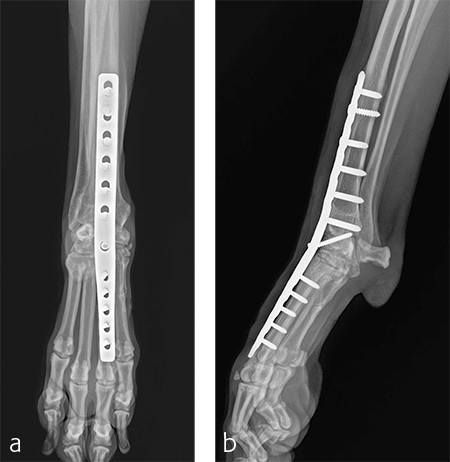

A custom fiberglass palmar splint was applied from the paw to just distal to the elbow after surgery. The splint was used for 4 weeks followed by a soft padded bandage for 4 weeks. Bandage changes were performed weekly. Activity was restricted to leash walks only for 12 weeks postoperatively. Radiographic examination 8 weeks after surgery revealed early healing of the pancarpal arthrodesis and stable implants. No complications were noted (Fig 6).

The patient was returned to normal activity 4 months after surgery. Radiographic examinations at 6 and 6.5 months after surgery revealed stable implants and fusion of the carpus (Fig 7 and 8). Functional outcome was excellent 1 year postoperatively. The patient had returned to full weight-bearing without lameness and the carpus was pain-free and stable.

Immediate postoperative images confirmed anatomic alignment and adequate carpal extension (Fig 10). At the 11-week postoperative follow-up examination, functional recovery was very good with images revealing stable implants and healing of the arthrodesis (Fig 11). The dog was then allowed to return to normal activity.